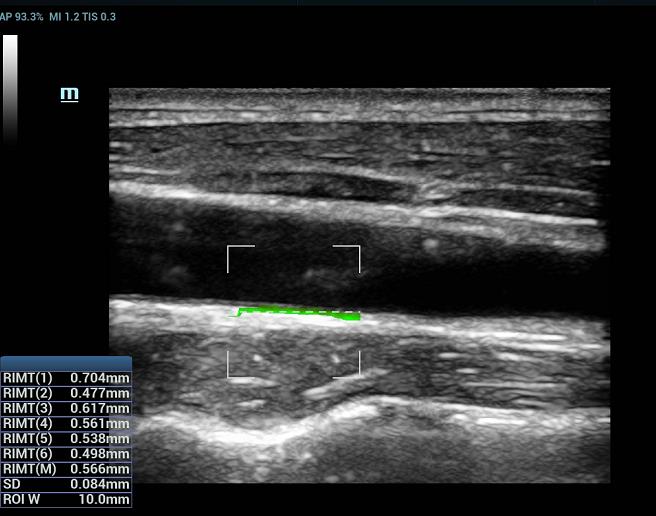

RIMT (RF-Data IMT — измерение толщины комплекса интима-медиа с помощью данных из радиодиапазона)

За счет содержащихся в необработанном акустическом сигнале данных из радиодиапазона (RF-Data), технология RIMT обеспечивает автоматическое измерение толщины КИМ в режиме реального времени с исключительно высокой точностью до 5 мкм, с количественным анализом в пределах 6 сердечных циклов и с меньшей зависимостью от качества изображения – все это значительно повышает точность диагностики.

• 09 Auto IMT

Авто IMT (толщина интимы-медии)